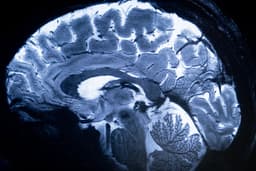

Timely Epilepsy Diagnosis Unlocks a Future of Independence and Confidence

As of 2025-11-17T06:34:32+00:00, the early diagnosis of seizures remains one of the most critical steps in improving the quality of life for people with epilepsy, particularly children. When seizures are identified and treated at an early stage, it not only helps control the episodes but also prevents long-term complications such as cognitive impairment, behavioral issues, and a decline in learning ability or IQ.

However, the symptoms of seizures in children can often be subtle and easily overlooked. Parents may dismiss brief staring, unresponsiveness, or unusual movements as minor quirks or tiredness. These small episodes may actually be absence seizures or focal seizures, which, if left untreated, can disrupt normal brain function. Over time, repeated unnoticed seizures can lead to irreversible cognitive decline, impacting memory, attention span, and overall development.

Early diagnosis also helps demystify the condition, reduces fear and anxiety, and enables patients to receive appropriate anti-seizure medications. Treating epilepsy early can also alleviate associated mental health problems like depression and anxiety, restoring confidence and emotional stability. Prompt initiation of anti-seizure medication significantly improves long-term outcomes, preventing the progression to drug-resistant epilepsy.